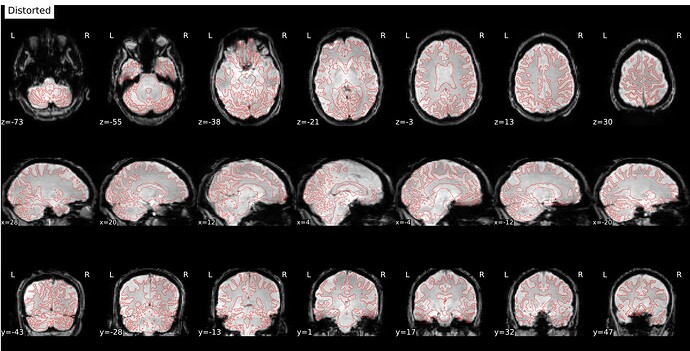

I’m seeing an apparent misalignment in the fmapCoreg reportlet for a PEPOLAR (SE-EPI AP/PA) distortion-correction workflow

- The SDC before/after panel looks okay-ish, suggesting distortion correction itself is likely working somehow, but poor than for subjects where fmap-bold coreg works as expected.